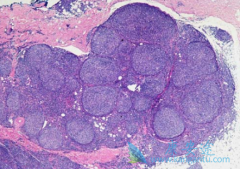

美罗华 (Rituximab)维持对B细胞淋巴瘤的作用存在争议。我们通过回顾各种临床试验的数据对美罗华维持在滤泡,弥漫大B和套细胞淋巴瘤中的效果和安全性进行了荟萃分析。在PubMed,ASCO和ASH数据库中查找相关临床研究,调查滤泡、弥漫大B和套细胞淋巴瘤美 ...